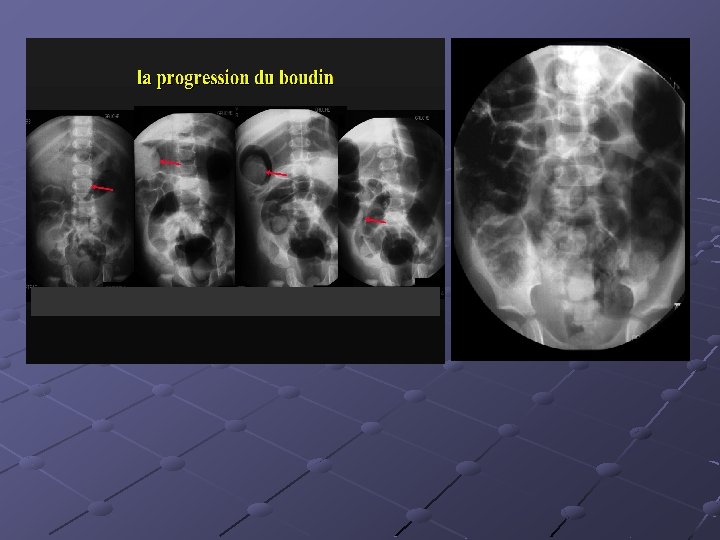

Cas n° 5 17 mois Histoire médicale antérieure = o Pleurs, douleurs abdominales

3, 7 x 2, 8 cm Depuis le rectum hypochondre gauche

INVAGINATION INTESTINALE AIGUE (IIA) Télescopage et penetration d’ un segment intestinal dans le segment d’ aval. Urgence diagnostique et thérapeutique: compression vasculaire ischémie et nécrose Nourrisson ( 80 % entre 6 mois et 2 ans ). Maximum entre 4 et 12 mois (I). Avant 3 mois ou après 5 ans (II). Prédominance masculine ( 3 G/2 F).

Idiopathique ( 90% des cas ): adénolymphite mésentérique(caractère saisonnier ) Secondaire: lymphome digestif, meckel, duplication digestive , polype , purpura rhumatoïde , troubles fonctionnels post chirurgicaux , impactions digestives ( mucoviscidose. . ) Formes anatomiques: iléo-iléale n iléo-colique n Appendico-colique n colo-colique n diam. boudin < 20 mm diam. boudin > 25 mm Diagnostic = échographie et non l’ASP Traitement: - Lavements (air, hydrosoluble, eau) - Chirurgie Contre-indications des lavements: péritonite, choc